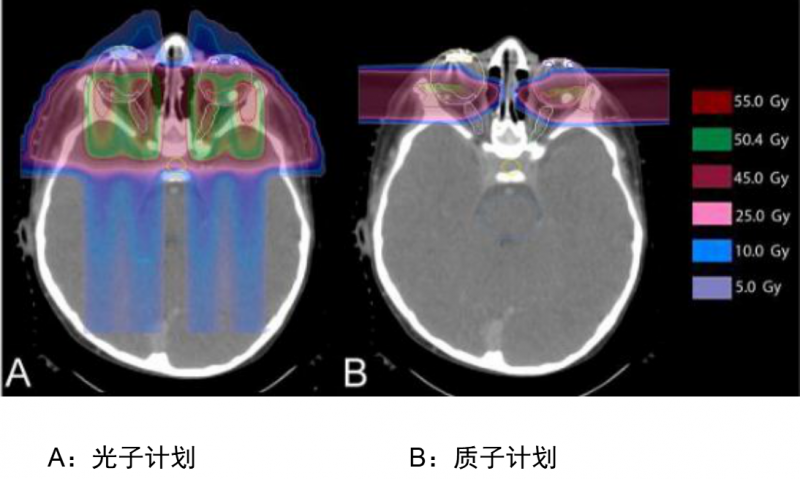

质子治疗在儿童脑瘤治疗中占有重要的地位,儿童癌症患者治疗一般都可以达到长期存活的目的,而治疗后的远期副作用是首要考虑的。质子治疗对比其他放疗能减少副作用的发生,包括智力、语言、听力和身高等方面的影响,确保患儿能在一个良好的体质下高质量生存,更能降低二次癌症的发生。我们从更加高深的层面质子治疗与传统放疗的原理——剂量分布差异来了解一下儿童质子治疗的优势:

解析:这个是儿童颅咽管癌的IMRT(上图:调强放疗,一种传统放疗的高端模式)与质子治疗(下图:Proton Therapy)的照射剂量分布比较,我们看箭头的指示,传统放疗照射剂量波及的范围很大,虽然颜色很淡(蓝色表示剂量低,黄色表示剂量高),但是需要多个方向同时照射才能达到肿瘤部位的致死剂量,对病灶周边正常组织的危害很大,容易引起严重的副作用,而质子治疗对健康组织的影响会小很多。